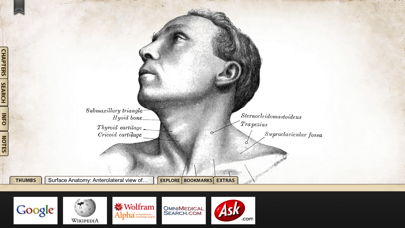

1. 'Gray's Anatomy', the renowned classic anatomical book by Henry Gray was first published in 1858 and is considered by many to be one of the most iconic and significant medical books of all time.

2. Gray's Anatomy is now available on the iPhone and iPod Touch using the highest resolution images possible.

6. We recommend this app for Doctors, Nurses, Students, Teachers and anyone who is interested in the wonder and complexity of the human body.